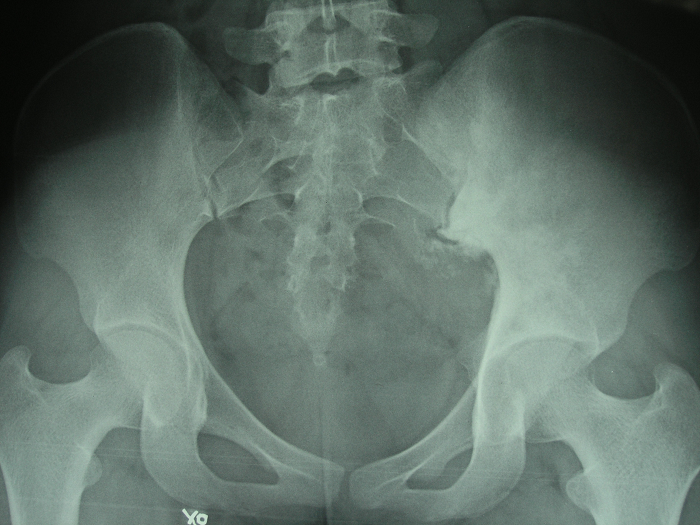

6、病例6:女 18岁 左半骨盆骨肉瘤,全身及肿瘤局部选择性动脉灌注大剂量化疗后行肿瘤切除人工半骨盆假体置换术

图 33 术前X线片

图 34、35、36 术前CT:肿瘤体积巨大,压迫

输尿管、膀胱等盆腔脏器

图 37 术前MRI

图 38 术前ECT

图 39 术前DSA

图 40 术前动脉化疗装置

图 41 肿瘤标本

a:外观象 b:剖面象

图 42 术后X线片